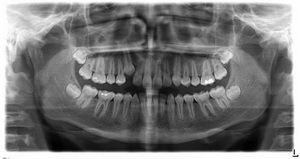

Начальным этапом диагностики артроза челюсти являются осмотр и анализ жалоб пациента, выявление асимметрии лица, пальпация жевательных мышц. Для уточнения диагноза, определения локализации и степени поражения хрящевых структур челюстного сустава проводится инструментальное обследование.

Инструментальная диагностика артроза челюсти включает проведение:

- рентгенографии;

- компьютерной томографии;

- магнитно-резонансной томографии.

Все эти методы позволяют обнаружить характерные симптомы артроза: истончение хрящевой прослойки, эрозии, трещины и другие дефекты на поверхности хряща, разрастания остеофитов, деформацию суставных структур.

Чаще всего диагноз ставят на основании результатов рентгенографии. Однако этот метод не позволяет оценить состояние и выявить поражение близлежащих мягких тканей. Поэтому при необходимости дополнительно может проводиться КТ или МРТ.

Для определения стадии развития заболевания, его локализации чаще других используется рентгенография. Рентгеновский снимок позволяет увидеть возникшие деформации, разрастания костей, изменения их формы. Реже применяются КТ, электромиография, контрастная рентгенография или брекеты (ортодонтические скобы).

Диагноз ставится на основании данных, полученных в ходе объективного осмотра, пальпации, аускультации и рентгенографии. Последняя является основным методом при диагностировании артроза ВНЧС. Благодаря ей заметны первые патологические изменения в суставе. Более точную информацию о его состоянии даст томография.

Из дополнительных исследований при болезнях ВНЧС рекомендованы:

- электромиография;

- артрофонография;

- артрография;

- ортопантомограмма.